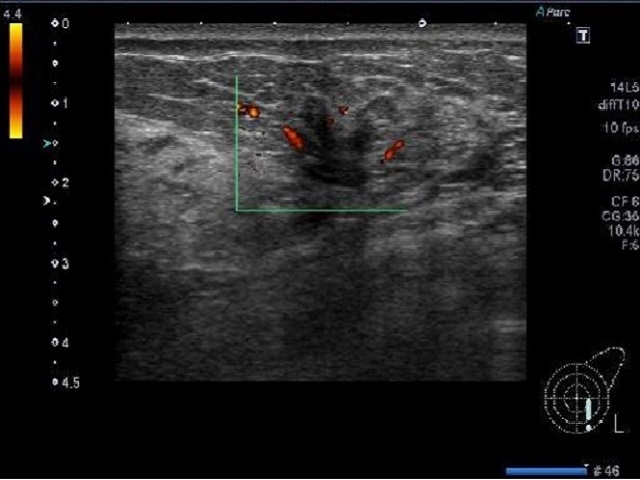

東大などが「人工知能を用いた医療画像と診療情報の統合による高精度な疾患画像判別モデルの開発」を発表。AIを用いて超音波検査画像と診療情報を統合する疾患画像判別モデルを開発。